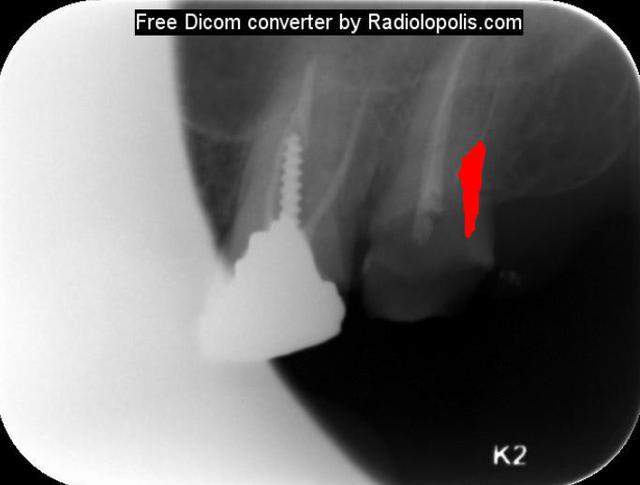

Dans ce cas : la radio est vraiment démonstrative, genre ça saute aux yeus (d'ou l'interet de poster ses radios) : la lime est completement courbée à l'opposé de la paroi correspondante au canal. Il "suffit" donc de supprimer completement le triangle de dentine empechant la lime d'être plus axée dans le canal, idéalement contre la paroi oposée à la courbure : ainsi on supprime cette 3eme contrainte mécanique entrainant les fractures.

Pour la recup de l'instrument fracturé, dégage bcp le 1/3 coronaire autour (US, fraise fine : attention aux perfos), l'instrument gainé signifie qu'il plaque sur toute sa longueur, l'idéal en Rot continue c'est de faire travailler l'instrument sur une partie seulement de sa longueur dans son insertion, si les spires mordent sur une portion trop importante c'est blocage et fracture en torsion.

Je suis (presque) sur que rien qu'en alignant la paroi distale à la courbure du canal, l'instrument peut se retirer à la précelle.

Je ne comprends pas pourquoi tu voudrais utiliser du MTA. Sur la première radio on dirait que la limes est en dehors de la racine, le pronostic de la dent ne me parait pas très bon...